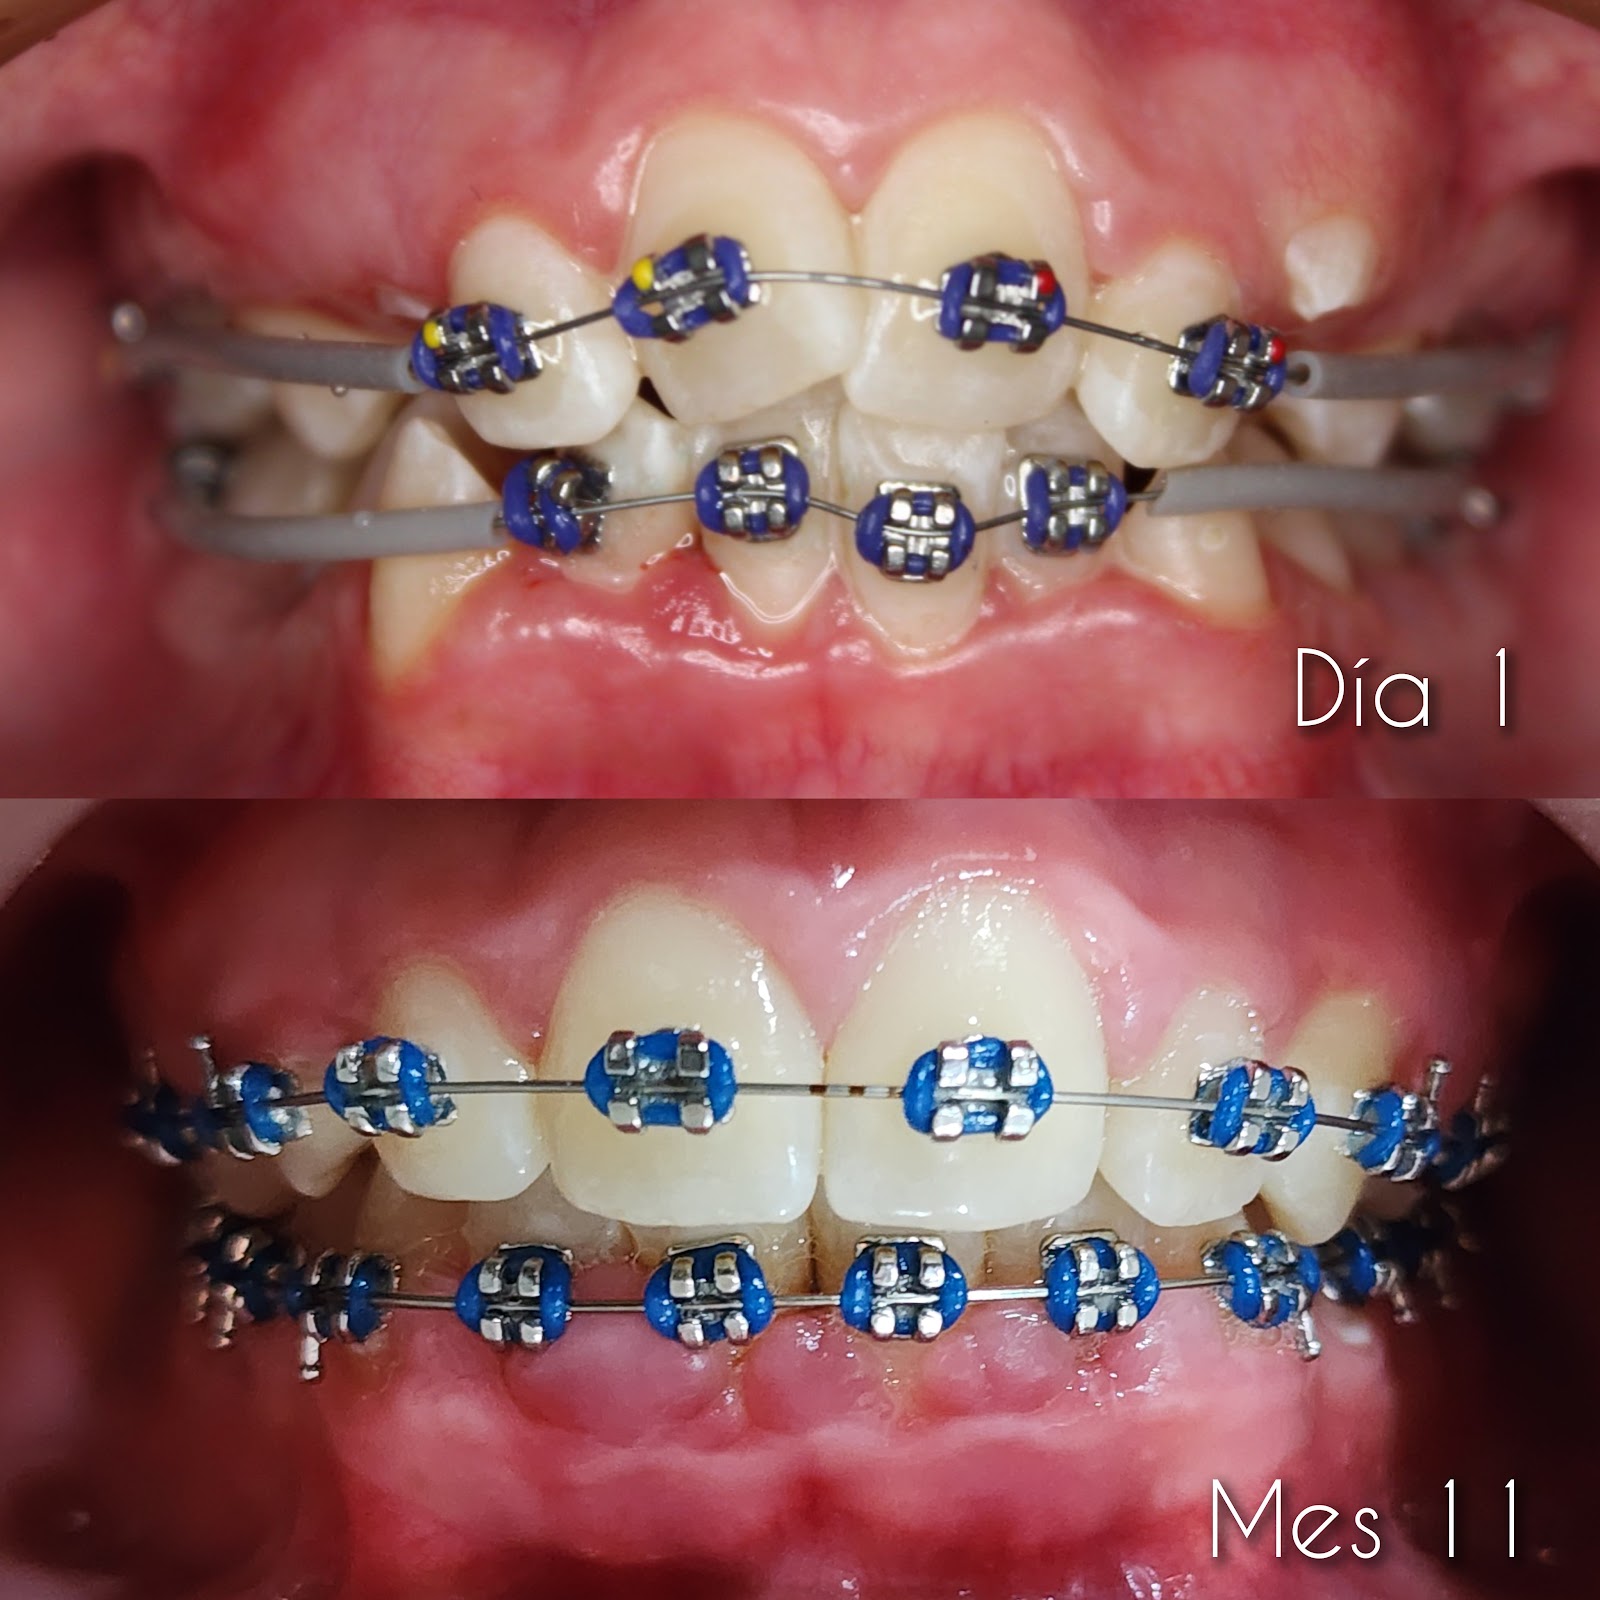

Clínica Dental El Sol, ubicada en Plaza Chelsea, Calle Ignacio Sandoval 1952, La Cantera, Colima, es un centro odontológico reconocido por su atención profesional y personalizada. Con una calificación perfecta de 5 estrellas basada en 27 opiniones, la clínica destaca por la calidad y claridad en la explicación de los tratamientos, lo que brinda a los pacientes tranquilidad y confianza. La Dra. Bárbara, especialista de la clínica, es valorada por su paciencia y dedicación durante cada consulta, asegurando un acompañamiento detallado en cada procedimiento. Los pacientes resaltan el servicio amable y la atención profesional que reciben, recomendando ampliamente sus servicios. La clínica ofrece un espacio cómodo y seguro para el cuidado de la salud dental, adaptándose a las necesidades individuales de cada persona. Para agendar una cita o solicitar información, puede comunicarse al teléfono 312 200 8173 o visitar su sitio web en directoriocolima.com. Clínica Dental El Sol es el punto de referencia en Colima para quienes buscan atención dental de calidad con un enfoque humano y profesional.

Clinica Dental El Sol, located at Plaza Chelsea, Calle Ignacio Sandoval 1952, La Cantera, Colima, is a well-regarded dental center known for its professional and personalized care. With a perfect 5-star rating from 27 reviews, the clinic stands out for the clear and thorough explanation of treatments, providing patients with peace of mind and confidence. Dr. Bárbara, the clinic’s specialist, is praised for her patience and dedication throughout every consultation, ensuring detailed support during each procedure. Patients highlight the friendly service and professional attention they receive, strongly recommending her services. The clinic offers a comfortable and safe environment for dental health care, tailored to the individual needs of each patient. To schedule an appointment or request information, call 312 200 8173 or visit their website at directoriocolima.com. Clinica Dental El Sol is a trusted point of interest in Colima for those seeking quality dental care with a human and professional approach.